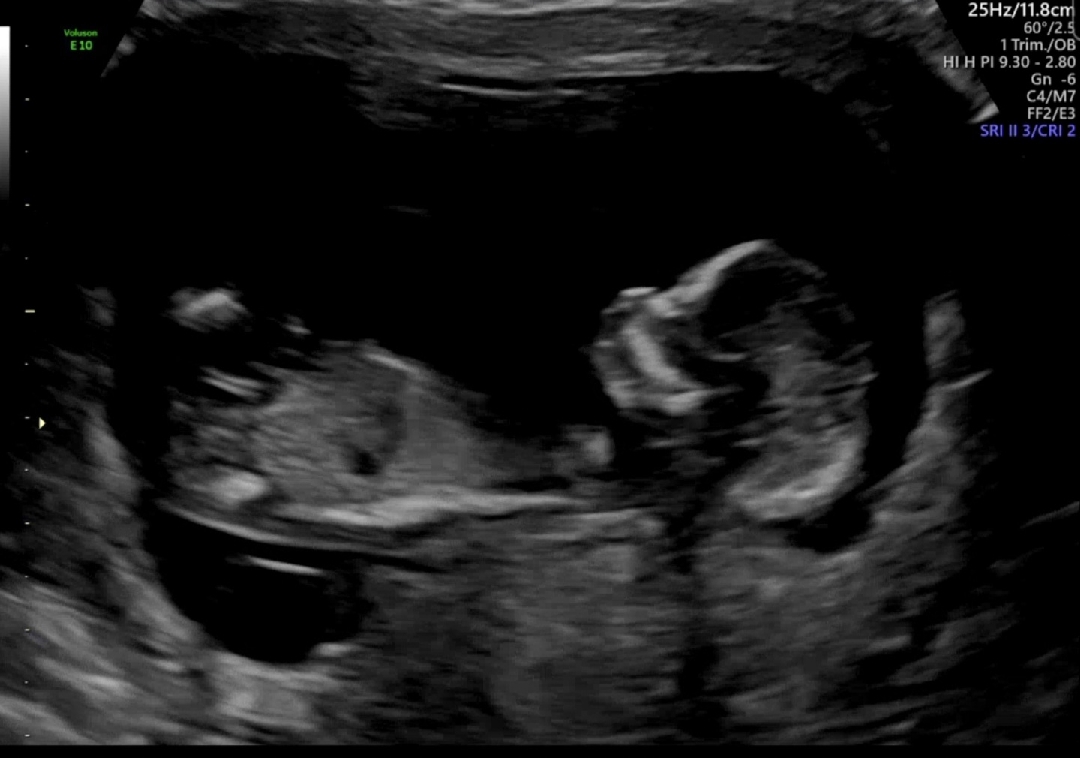

저 사진이 돌기가 맞을까요..? 12주 2일입니다

허벅지 뼈 같아요. 돌기는 안 보이네요